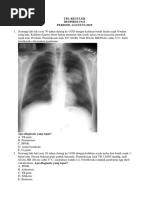

Seoranglaki-laki dibawa ke IGD RSUDZA dengan keluhan sesak napas

yang dialami sejak 5 tahun dantiba-tiba memburuk dalam 1 hari

terakhirini.

Sesak

napas

bertambahberatsaatberaktivitas.Pasienjugamengeluhkanbatuk

yang

disertaidahakberwarnaputihsejaksemingguterakhir.

Pasienmemilikiriwayatmerokokselama 55 tahun. Riwayat asma tidak

ada.Pada pemeriksaan fisik didapatkan tekanan darah 120/80 mmHg, nadi

90x/I, RR 30x/I, suhu axillar 36.6C. inpeksi tampak dada kiri dan kanan

tampak simetris,palpasi stem fremitus dada kiridankananmelemah,

perkusihipersonor,

auskultasi

terdengar

ekspirasi

memanjang

danrhonkipadakedualapangparu. Pada foto thorak menunjukkan tampak

corakan kasar dikedua paru.

Apakah kemungkinandiagnosis yang tepat pada pasien ini?

A. Asma bronchial

B. Asmacardial

C. PPOK eksaserbasi akut

D. Tuberkulosis

E. Bronkitis

C